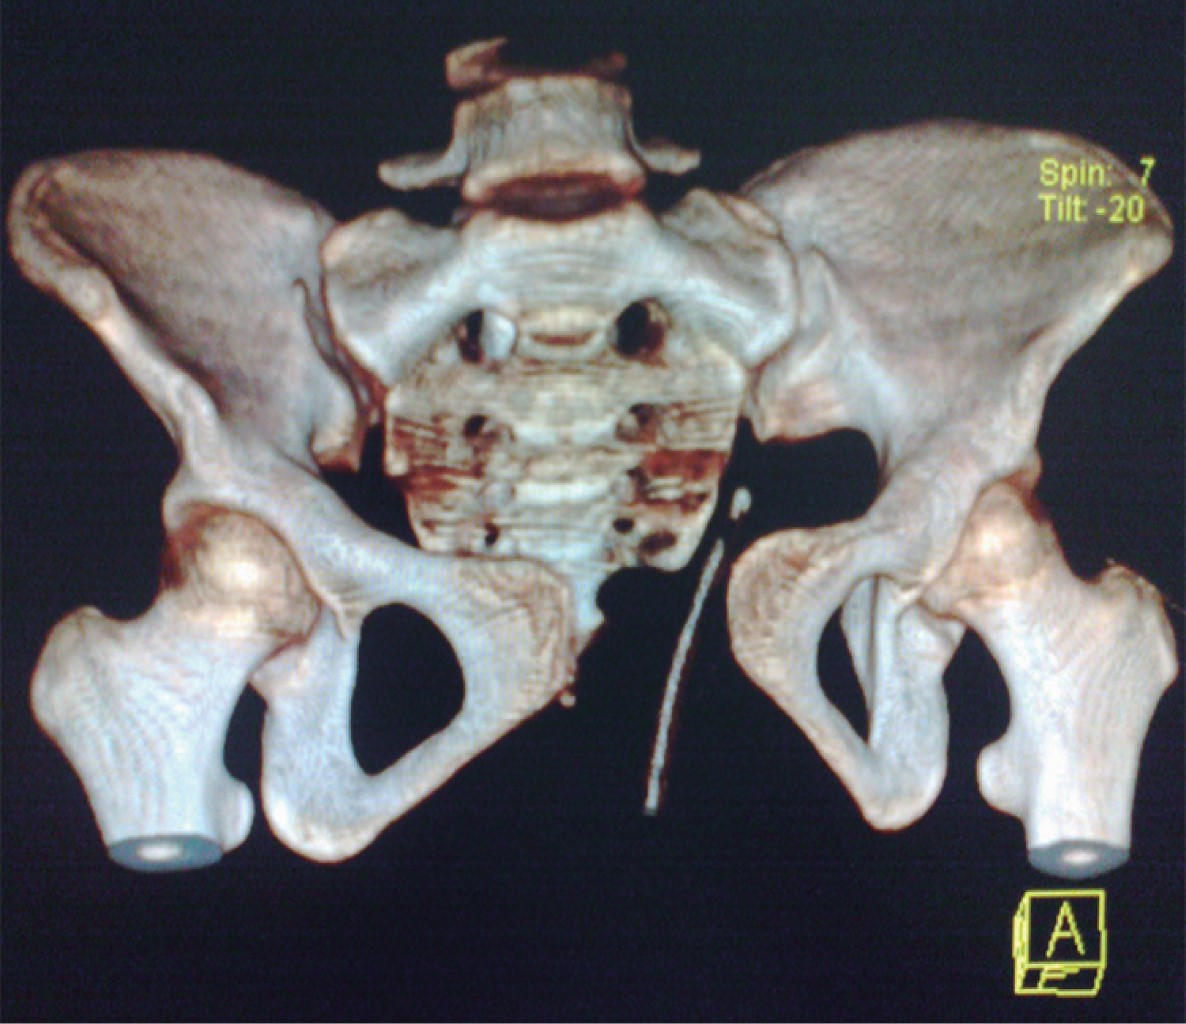

Radiológicamente, se detecta presencia de lesión a nivel de la sínfisis del pubis con una separación de 5.5 cm, se advierte falta de fusión a nivel de ambas crestas iliacas, de igual manera en la tomografía axial computarizada de reconstrucción se corrobora la lesión púbica y lesión a nivel de las articulaciones sacroiliacas en los ligamentos anteriores (Figuras 1 y 2).

Motivo por el cual se procedió a iniciar manejo quirúrgico mediante la realización de una reducción abierta y colocación de dos placas DCP (placas de compresión dinámica) 3.5 mm de cinco y cuatro orificios en la superficie anterior y superior del pubis, respectivamente como medio para estabilizar el anillo pélvico. La lesión de la articulación sacroiliaca se manejó de forma conservadora (Figuras 3 y 4), no se presentó ninguna complicación en el transoperatorio y evolucionó de la misma manera durante su estancia hospitalaria.